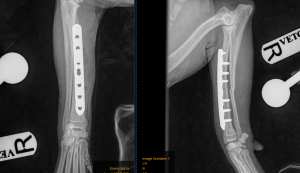

To repair the fracture, a surgical approach was made to the radius. Once the broken bone was realigned (reduced), it was stabilised using a metal plate and screws. Radiographs taken after surgery confirmed that the fracture had been accurately reduced and the implants were positioned correctly.

Immediate post-op X-rays